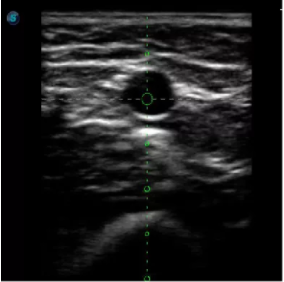

1生殖專用探頭

傳統(tǒng)腔內(nèi)探頭采用直柄設(shè)計,在搭配穿刺架使用時,手術(shù)空間小,不易操作;生殖專用的曲柄探頭,探頭柄采用彎曲成角度設(shè)計,可實現(xiàn)監(jiān)視、取卵兩不誤,搭載穿刺架時,可以清晰顯示穿刺針的進針過程、深度和位置,實時監(jiān)視取卵全過程,保障取卵操作精準與安全。

取卵臨床圖